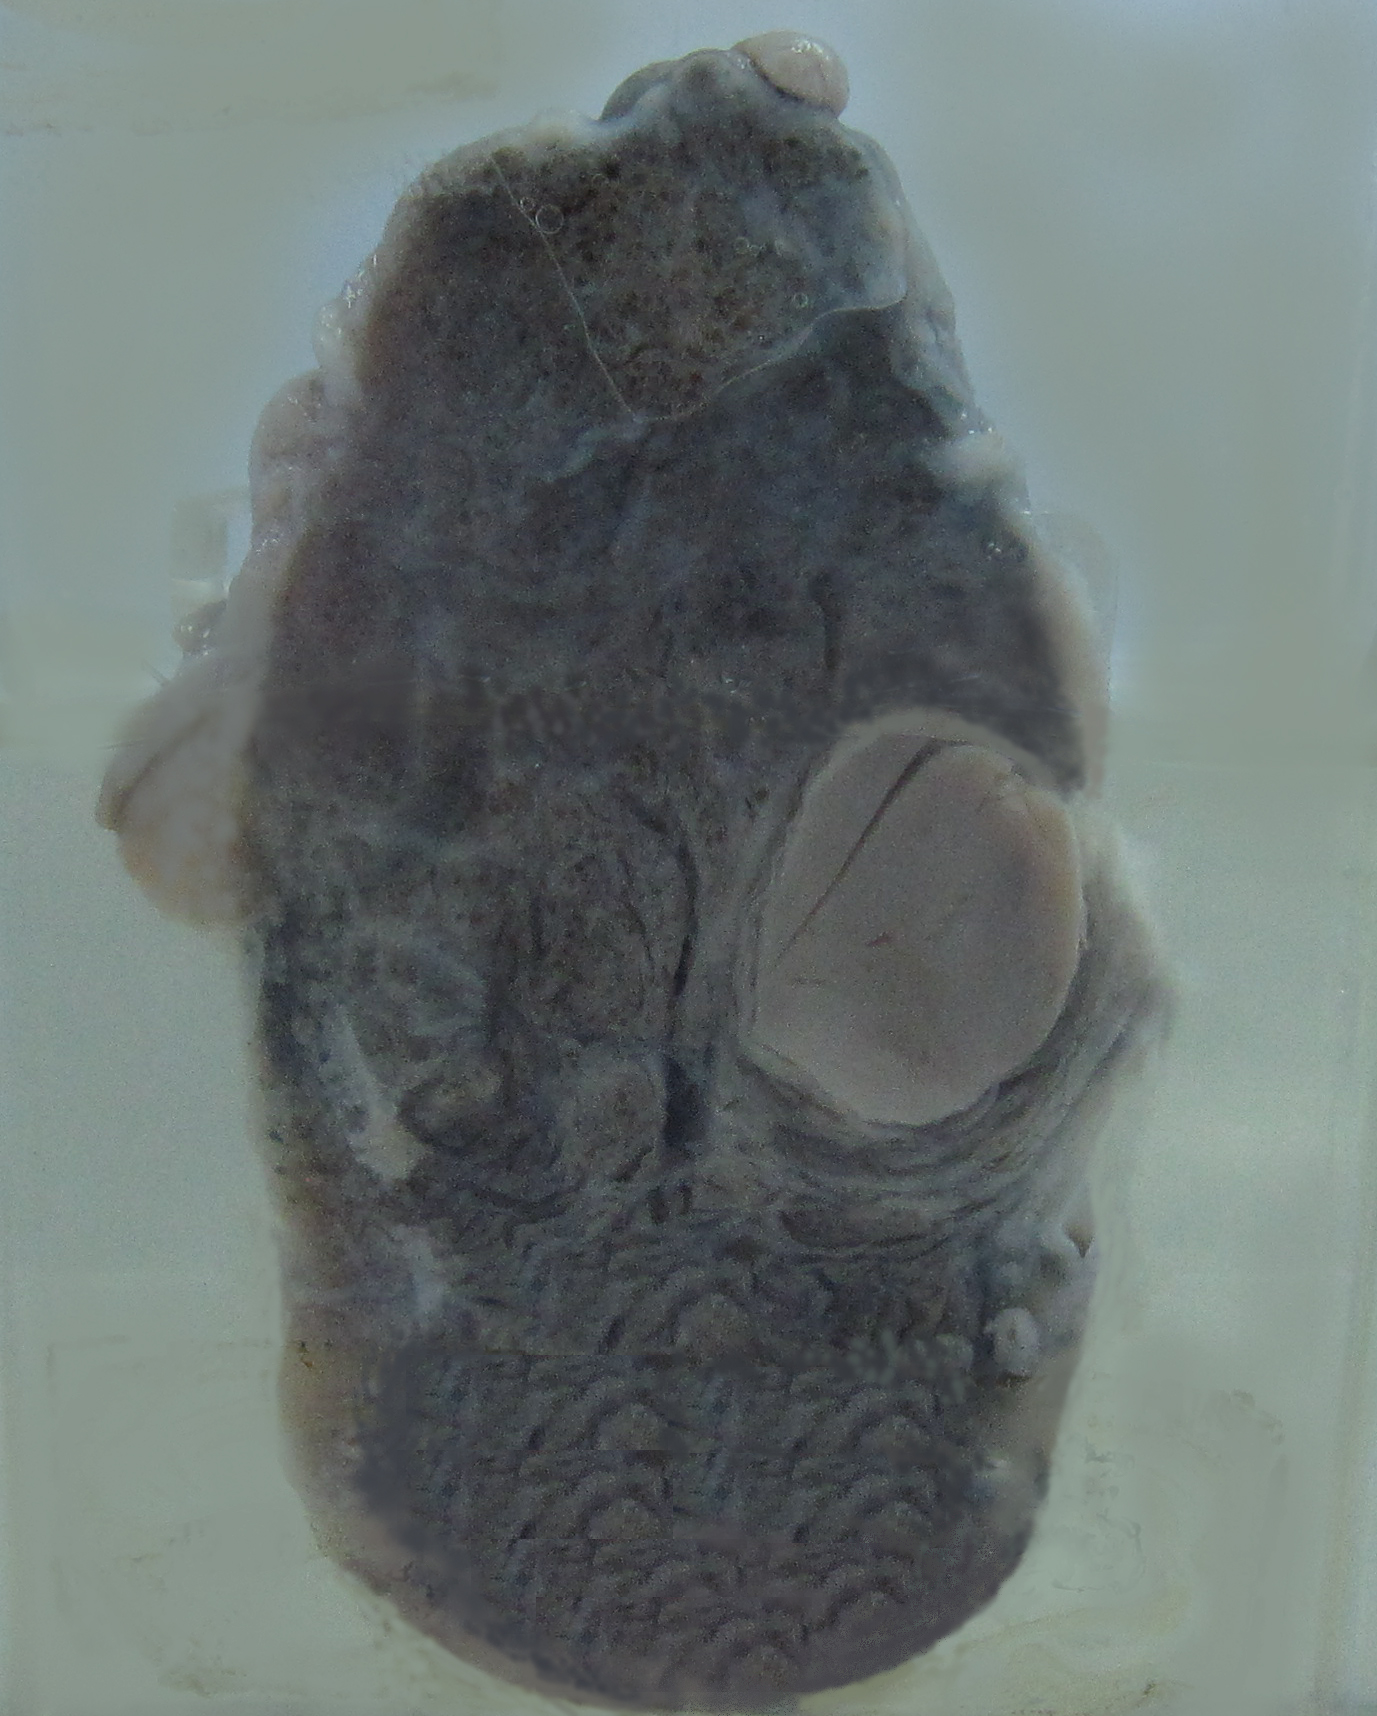

5.甲状腺腺瘤